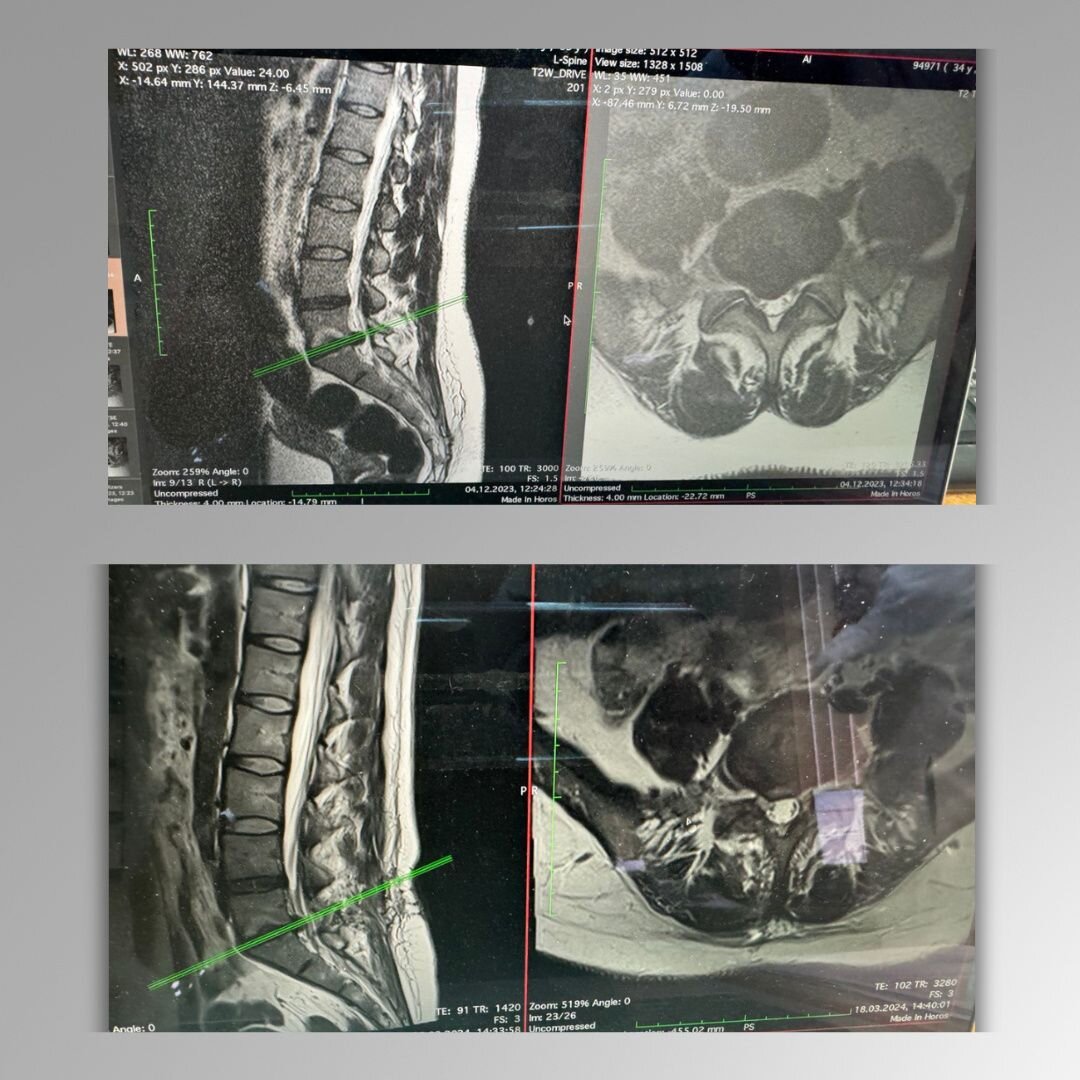

Почему так произошло? В данном случае на МРТ мы увидели не рецидив, а так называемую «псевдогрыжу» — перерастянутую продольную связку, которую рентгенологи иногда интерпретируют как рецидив.

Это очень частая история. После операции некоторое время сохраняется воспаление и отек тканей и другие послеоперационные изменения, которые могут проявлять себя болями, похожими на боли при грыже. И МРТ в этот период (от 1 до 3 месяцев) я делать не рекомендую, поскольку сами видите — он неинформативен.